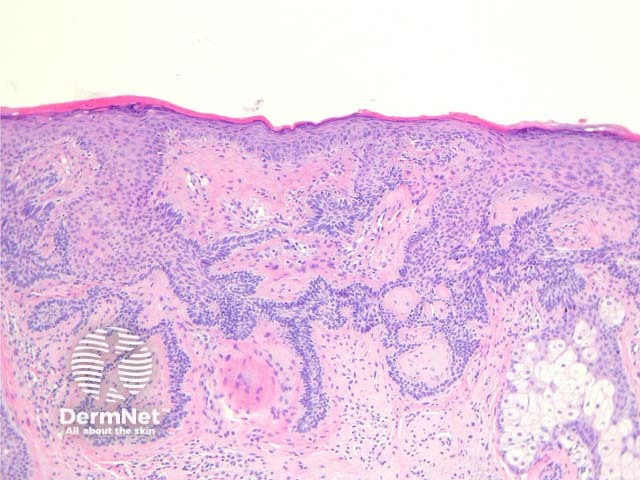

In tumour of the follicular infundibulum, sections show an acanthoma composed of pale pink cells and sometimes clear cells. The tumour forms anastomosing narrow strands that run parallel to the epidermis. These strands have peripheral palisading of basaloid cells (figures 1, 2).

Figure 1